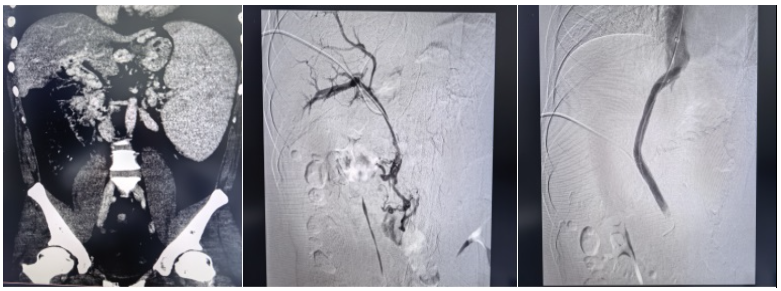

近日,中南大学湘雅三医院放射介入团队在副主任(主持工作)梁琪的带领下,成功完成一例国内罕见的超高难度经颈静脉肝内门体分流术(TIPS)。该手术突破介入诊疗临床极限,为被致命出血风险困扰7年的患者重建生命通道,彰显了医院在复杂门静脉高压、疑难血管疾病介入诊疗领域的实力。

本次接受手术的患者年仅29岁,2019年确诊门静脉血栓继发门脉海绵样变。7年来,患者饱受严重门静脉高压、食管胃底静脉曲张折磨,随时面临上消化道大出血的致命风险。因病情极度复杂、血管条件极差,患者辗转全国多地求医,均因手术风险极高、常规术式无法实施而被拒诊,救治之路一度陷入绝境。

此次手术被业内视为介入领域的“极限挑战”,核心难点在于患者极为罕见的血管条件:门静脉主干完全闭塞,门脉海绵样变,脾静脉与肠系膜上静脉广泛血栓充填,常规TIPS手术缺乏有效流入道,标准穿刺路径完全失效。在血管解剖结构破坏、解剖标志模糊、血栓弥漫充填的极端条件下,从零构建肝内分流通道,对术者的操作精度、临床经验与应急处置能力均提出极高要求。

“没有通道,我们就为生命开辟一条通道。”面对患者与家属的殷切期盼,梁琪带领吴作为、骆雷等核心团队成员毅然迎难而上。术前,团队反复研读影像学资料,全面评估血管条件与手术风险,制定了周密的个体化手术方案。术中,团队凭借深厚的介入诊疗功底,沉着操控、精准穿刺,在闭塞多年的血管中耐心探查、精细开通,成功将支架置入门静脉主干并建立肝内分流道,显著降低门静脉压力,从根源上解除致命大出血风险,实现微创、安全、高效救治,疗效远超家属预期。